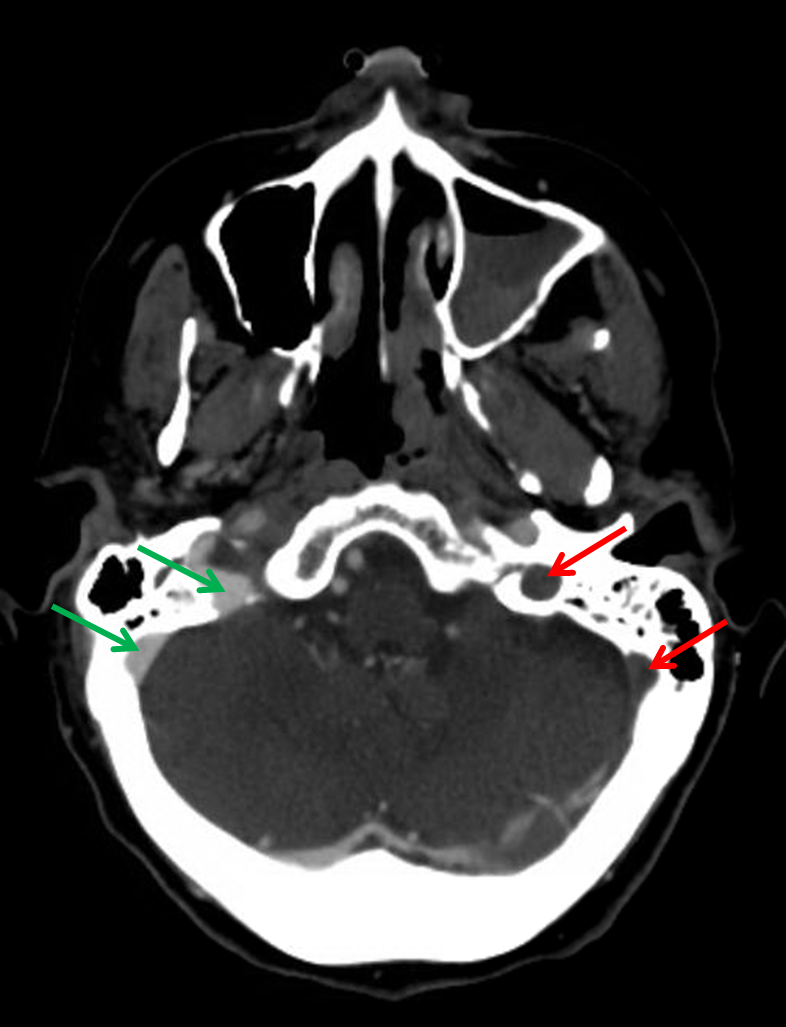

Diagnostic Value of Multidetector-Row CT Angiography in ...

Diagnostic Value of Multidetector-Row CT Angiography in ... from www.ajnr.org